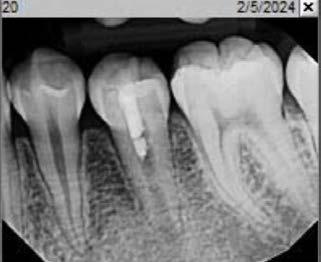

Employing revascularization by infiltrating stem cells from apical papilla and using them to treat immature necrotic tooth with periapical infection promotes root development and reduces fracture risk. Case report.